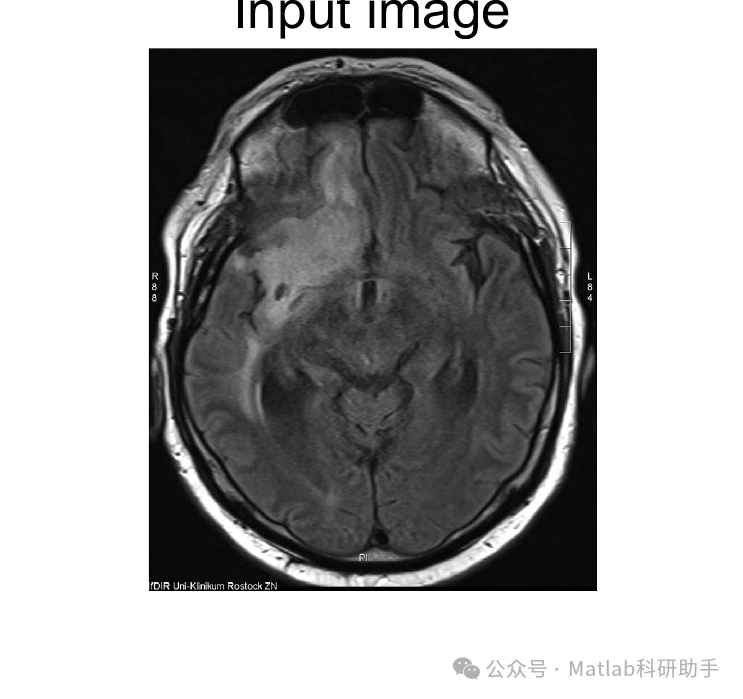

脑肿瘤是严重威胁人类生命健康的恶性疾病,其早期准确检测和精确分割对于制定有效的治疗方案、提高患者生存率具有举足轻重的作用。磁共振成像(MRI)作为一种非侵入性、高分辨率的医学影像技术,已成为脑肿瘤诊断的金标准。然而,传统的人工诊断方法费时费力,且受限于医生经验,易出现主观偏差。近年来,随着计算机视觉和机器学习技术的飞速发展,特别是深度学习在图像处理领域的突破性进展,基于MRI图像的脑肿瘤自动检测和分割技术展现出巨大潜力。本文将深入探讨利用MRI图像进行脑肿瘤检测和分割的必要性、现有技术挑战、以及基于深度学习的解决方案,并展望未来的发展方向。

脑肿瘤是一种在颅内异常生长的细胞团块,根据其性质可分为良性和恶性。恶性脑肿瘤,如胶质母细胞瘤(Glioblastoma Multiforme, GBM),生长迅速,侵袭性强,预后极差。因此,对脑肿瘤的早期发现和精确描绘其边界(即分割)是神经外科手术规划、放射治疗剂量学以及化疗效果评估的关键前提。MRI图像因其卓越的软组织对比度,能够清晰地显示脑部结构和病变区域,被广泛应用于脑肿瘤的临床诊断。

然而,人工对MRI图像进行脑肿瘤的检测和分割,面临诸多挑战。首先,肿瘤的形状、大小、位置、病理类型以及浸润边界具有高度异质性,使得不同病例的特征表现差异巨大。其次,MRI图像获取过程中可能存在噪声、伪影以及偏置场不均匀等问题,影响图像质量。再次,人工分割需要医生耗费大量时间,且其结果受限于个体经验和疲劳程度,可能存在批内和批间差异。鉴于此,开发自动化、高精度、鲁棒性强的脑肿瘤检测和分割方法,成为当前医学影像分析领域的研究热点。